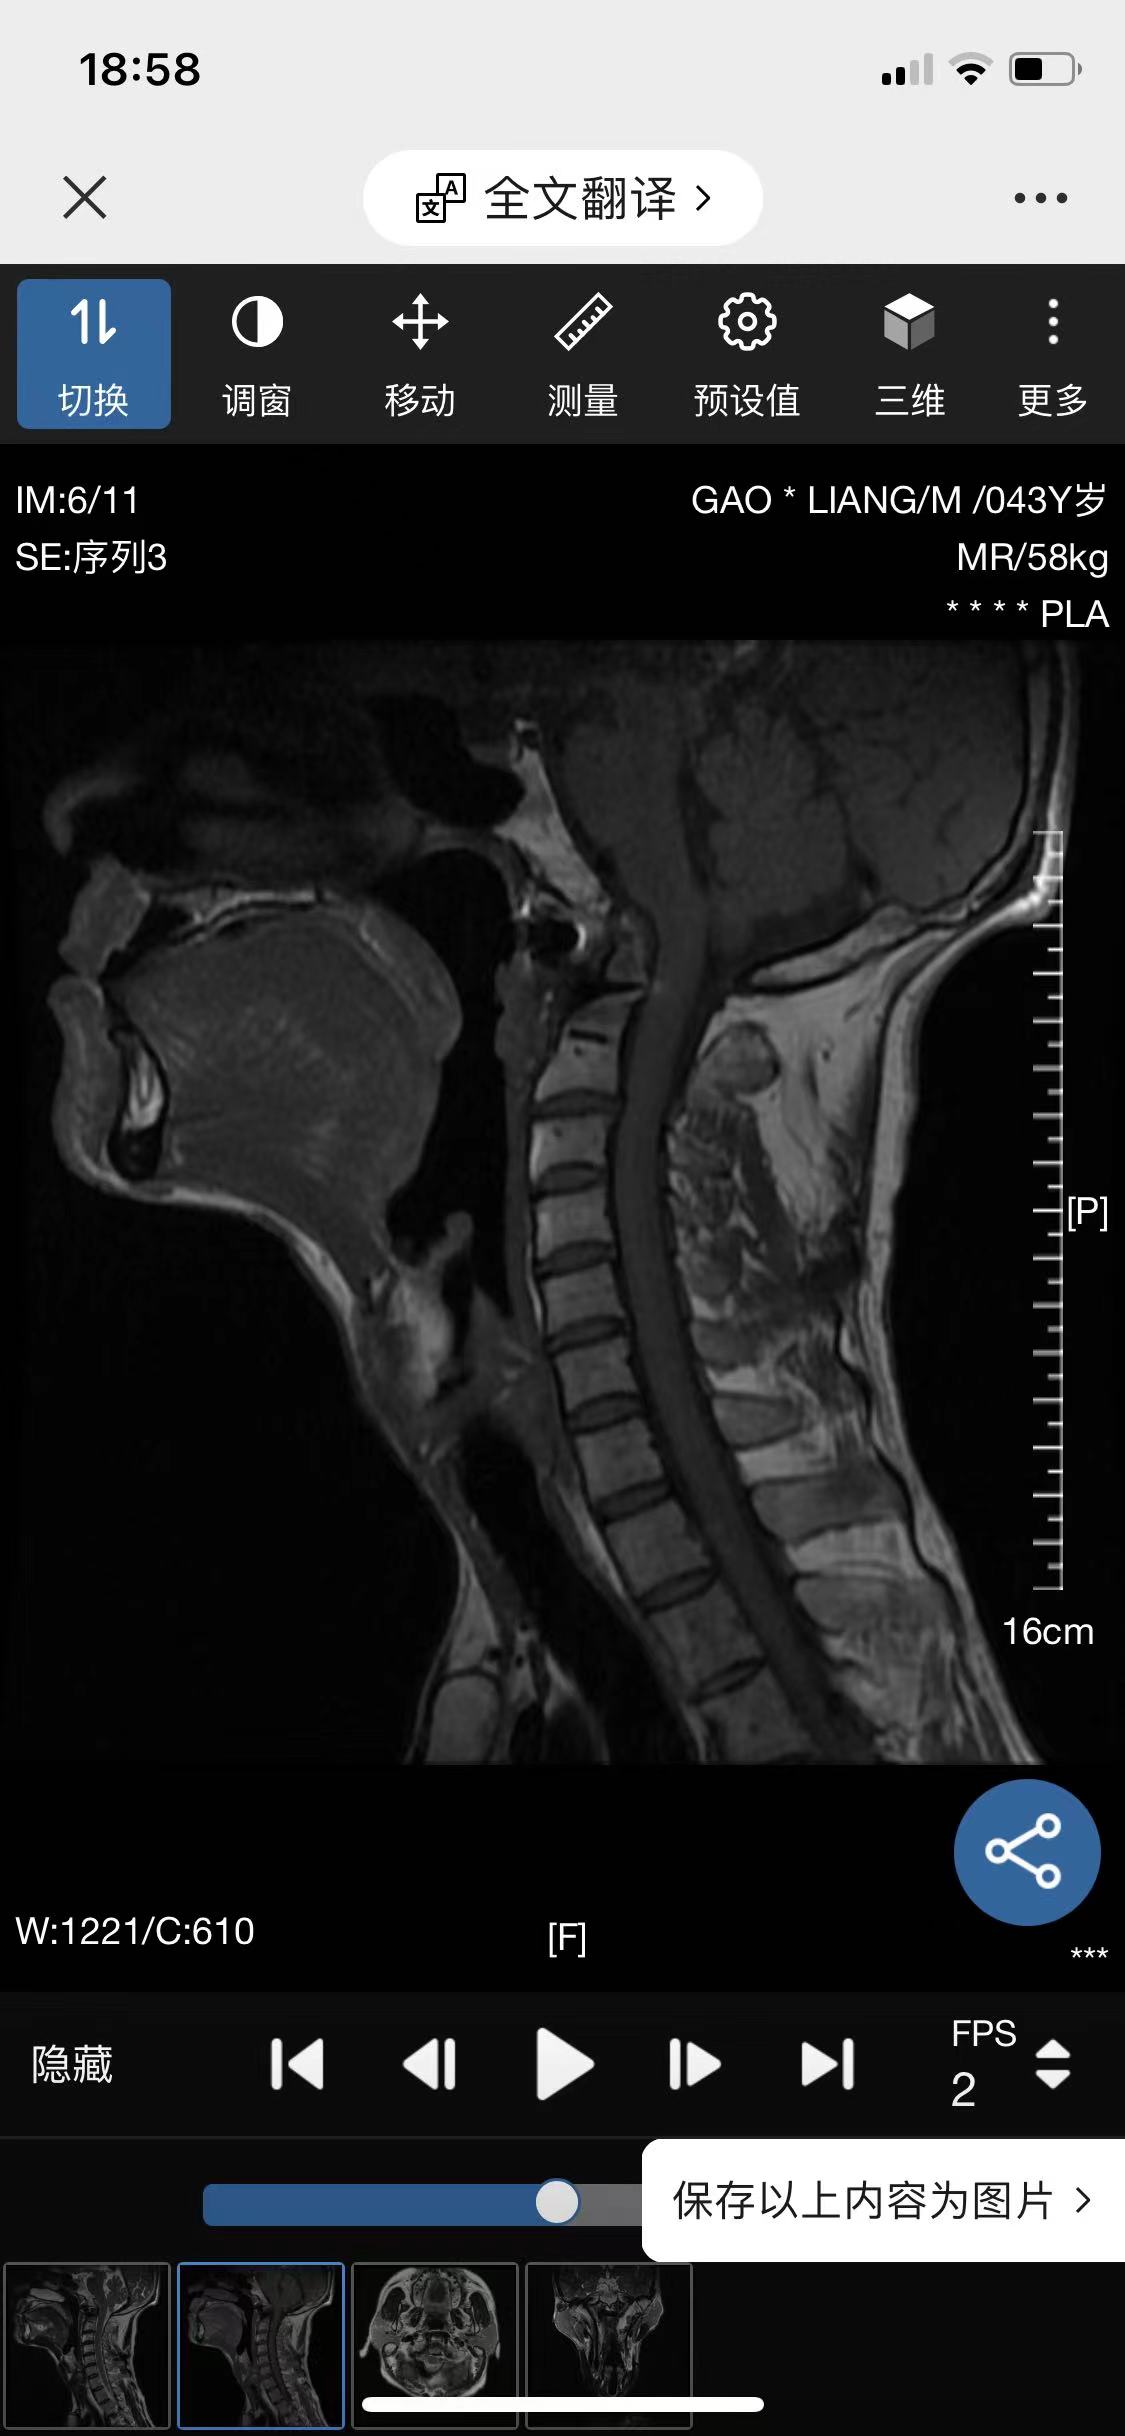

• 诊断:寰枢椎脱位

• 影像:

• 术后影像: